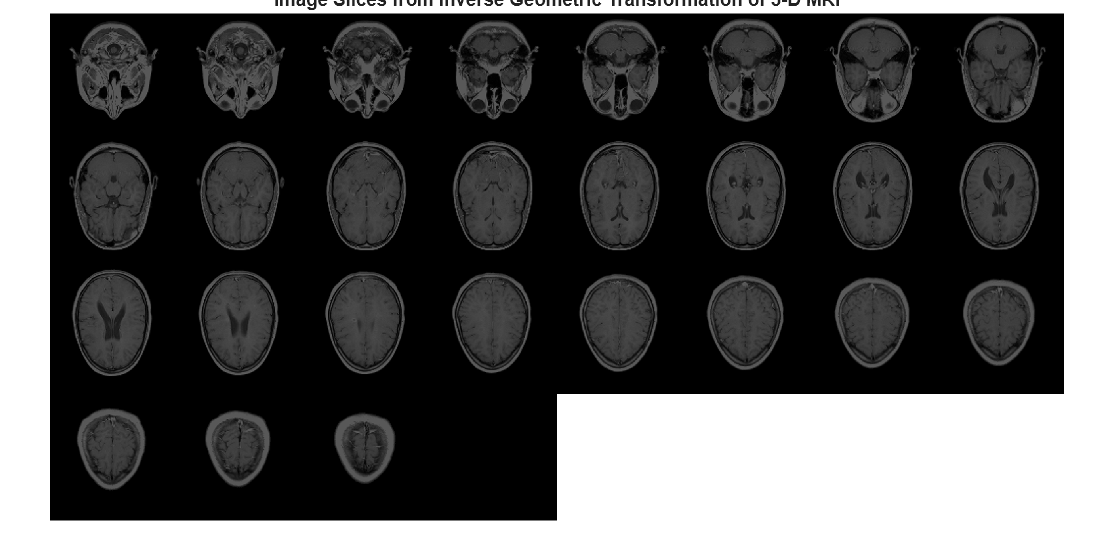

Examples